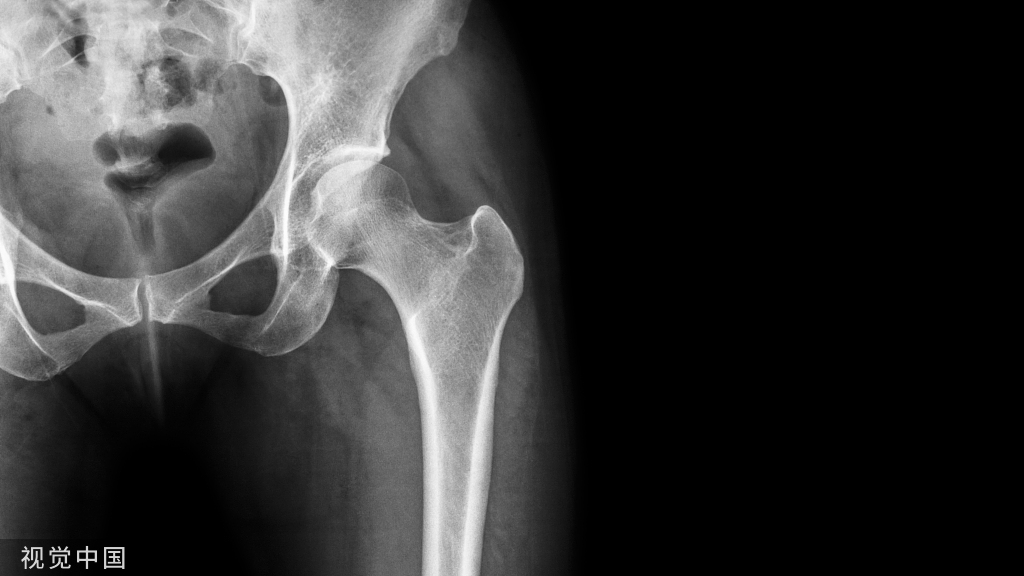

② 四踝骨折典型病例图。